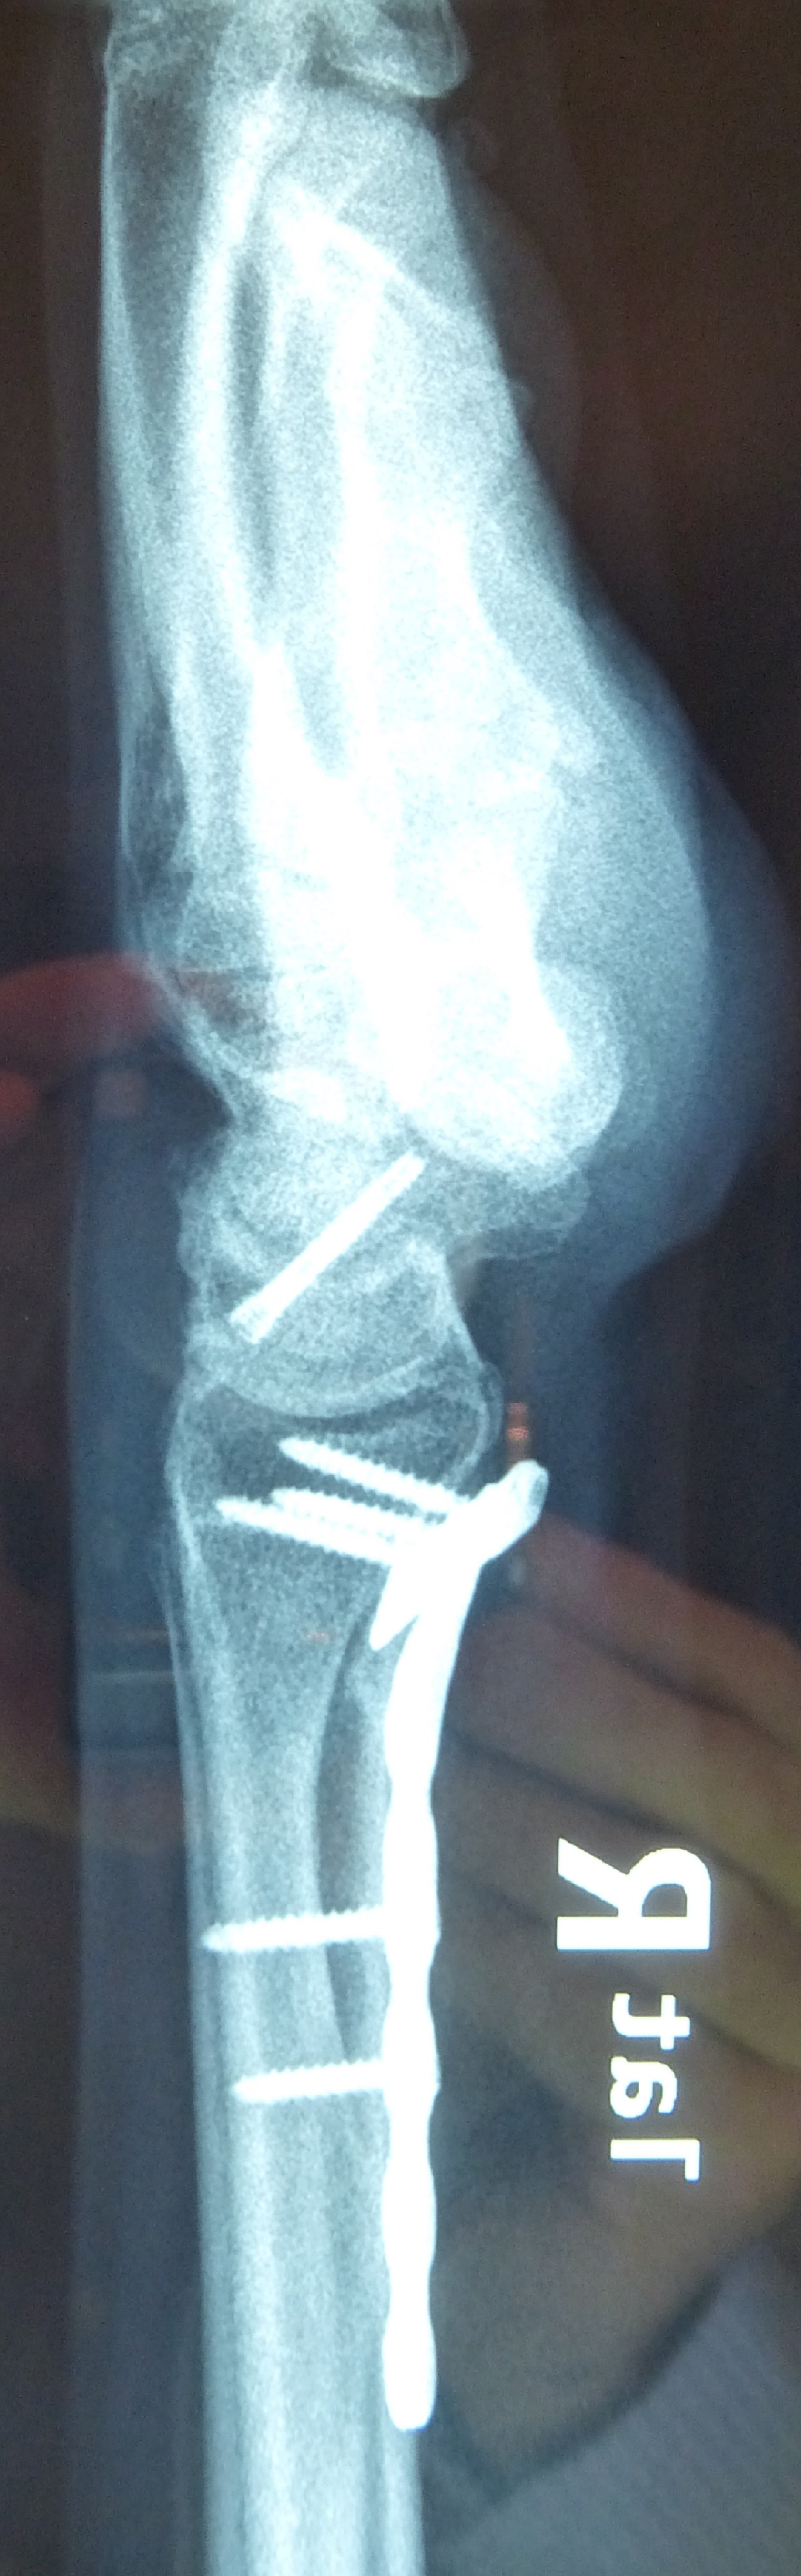

Η αντιμετώπιση της ψευδάρθρωσης του σκαφοειδούς είναι πάντοτε χειρουργική. Με ραχιαία ή παλαμιαία προσπέλαση αποκαθίσταται ο άξονας του σκαφοειδούς και σταθεροποιείται το σκαφοειδές με ειδική βίδα ή βελόνες, με παράλληλη τοποθέτηση οστικών μοσχευμάτων. Μπορεί επιπλέον να γίνει και οστεοτομία κλειστής σφήνας του περιφερικού άκρου της κερκίδος. Στις περιπτώσεις άσηπτης νέκρωσης το μόσχευμα πρέπει να είναι αγγειούμενο – για να προσδώσει αιμάτωση στο νεκρωμένο κεντρικό τμήμα – και λαμβάνεται με μικροχειρουργικές τεχνικές από το περιφερικό τμήμα της κερκίδος ή από άλλα τμήματα του σώματος

Διεγχειρητικά

Περίπτωση 2: Μετεγχειρητικά 1